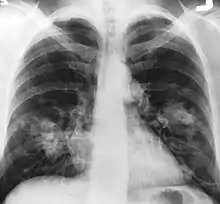

Radiographie de face du thorax montrant un probable cancer du poumon (taches claires sur le côté externe de chaque poumon).

Le cancer du poumon peut être vu sur les radiographies thoraciques et le scanner. Le diagnostic est confirmé par une biopsie. Ceci se fait généralement par bronchoscopie, ou par biopsie guidée par scanner. Le traitement et le pronostic dépendent du type histologique du cancer, de son stade (degré de dissémination), et de l'état général de santé du patient.